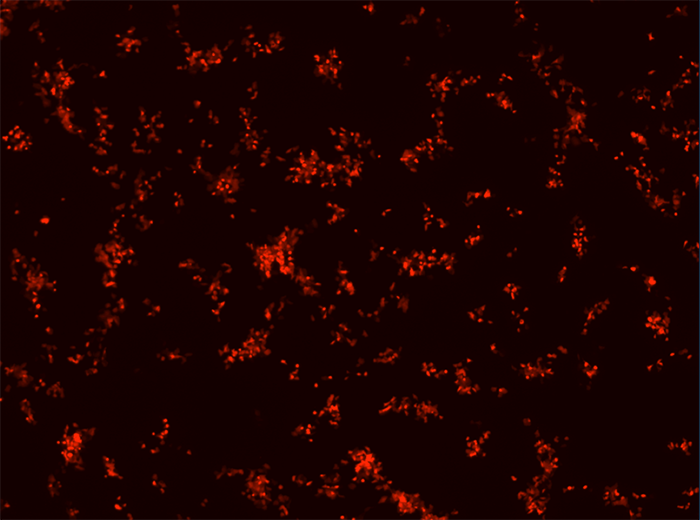

No hay ningún tipo de tratamiento para la mayoría de infecciones víricas. Por tanto, se necesitan urgentemente nuevos tratamientos antivirales. Actualmente, estamos utilizando plataformas de cribado de alto rendimiento para identificar inhibidores de importantes virus de ARN, incluyendo el SARS-CoV-2, el virus respiratorio sincitial, picornavirus y el virus de la gripe. Trabajamos con un nivel 2 de bioseguridad y condiciones de bioseguridad de nivel 3, y somos de los pocos grupos en Valencia que trabaja realmente con el virus SARS-CoV-2. En el marco de antivirales prometedores, llevamos a cabo experimentos para entender cómo funciona cada compuesto y examinar si la resistencia a estos últimos se desarrolla rápidamente. Trabajamos en colaboración con numerosos grupos, incluyendo químicos, biólogos computacionales y biólogos estructurales.